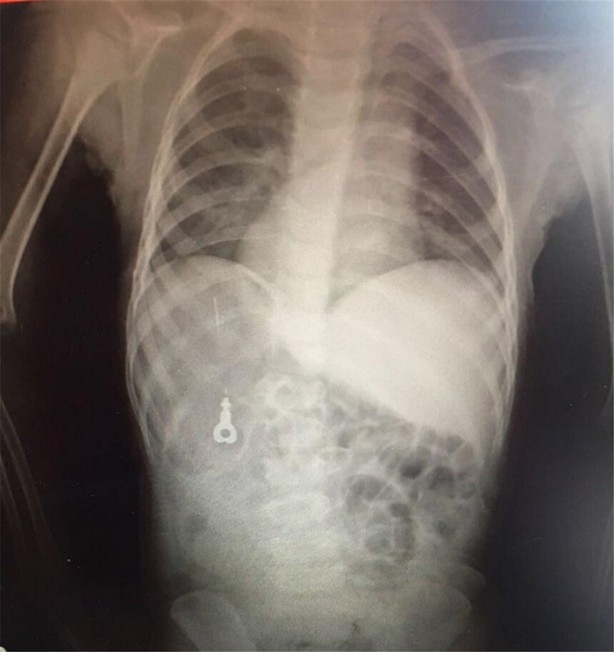

İzmir Tepecik Eğitim ve Araştırma Hastanesi Çocuk Gastroenteroloji Bölümü'nün, yabancı cisim yutan çocukların nefes ve borusu ile midelerinden çıkarttığı, anahtarlık, madeni para, saat pili, ataç, çengelli iğne ve çivi gibi objeler görenleri hayrete düşürdü.

Bu objelerden en tehlikelisinin piller olduğuna dikkat çeken Doç.Dr. Maşallah Baran, "Piller kimyasal mekanizmayla mukozayı yakıyor, özellikle yemek borusu çok duyarlı pillere, hele ki yeni takılmış bir pilse saatler içinde şahit olduğum bir kaç vaka var, yemek borusunu kömür haline getirebiliyor" dedi.